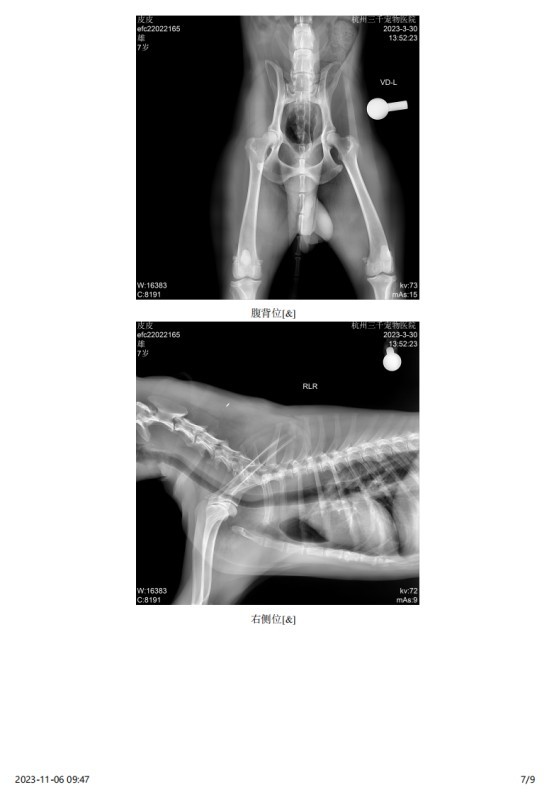

主诉最近发现两只睾丸的大小相差较大,精神状态尚可,挑食。于近日入院进行病变部位的超声检查,结果如图:

2023 年 3 月份检查结果